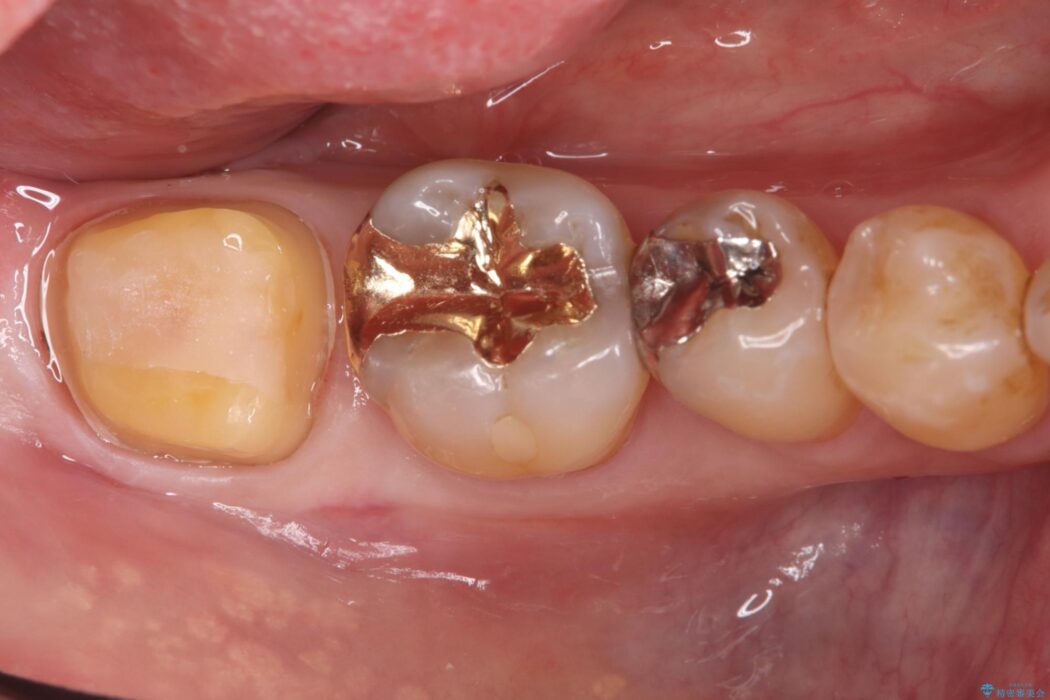

欠けた奥歯を土台から整え、金主成分の「PGAクラウン」で修復しました。PGAクラウンは、金を主成分とする合金でできており、非常に優れた特性を持っています。

欠けてしまった歯の構造的な弱点が解消され、患者様は硬いものでもしっかりと噛める、安心で機能的な奥歯を取り戻すことができました。